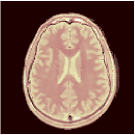

Ground truth (T1, T2, PD) anatomical maps acquired by the MAGIC gold standard [21]

T1 (sec) T1 error T2 (sec) T2 error PD (a.u.) PD error

Table 1 and Figure 2 compare the performances of the MRF baselines against our proposed PGD-Net using and 5 recurrent iterations. We also include inference results using the proposed encoder alone , without proximal iterations. Reconstruction performances were measured by the Normalised RMSE , MAE , Structural Similarity Index Metric (SSIM) [28], the required storage for the MRF dictionary (in DM methods) or the networks, and the algorithm runtimes averaged over the test image slices.

The non-iterative FGM results in incorrect maps due to the severe under-sampling artefacts. The model-based BLIP iterations improve this, however, due to lacking spatial regularisation, BLIP has limited accuracy and cannot fully remove aliasing artefacts (e.g. see T2 maps in Figure 2) despite 20 iterations and very long runtime. In contrast, all deep learning methods outperform BLIP not only in accuracy but also in having 2 to 3 orders of magnitude faster reconstruction times—an important advantage of the learning-based methods. The proposed PGD-Net consistently outperforms all baselines, including DM and learning-based methods, over all defined accuracy metrics. This is achieved due to learning an effective spatiotemporal model (only) for the proximal operator i.e. the and Bloch networks, directly incorporating the physical acquisition model H into the recurrent iterations to avoid over-parameterisation of the overall inference model, as well as enforcing reconstructions to be consistent with the Bloch dynamics and the k-space data through the multi-term training loss (6). The MRFCNN and SCQ over-parametrise the inference by 1 and 3 orders of magnitude larger model sizes (the SCQ requires larger memory than DM) and are unable to achieve PGD-Net’s accuracy e.g. see the corresponding over-smoothed T2 maps in Fig. 2. Finally, we observe that despite having roughly the same model size (storage), the encoder alone predictions are not as accurate as the results of the PGD-Net’s recurrent iterations. By increasing the number of iterations we observe that the PGD-Net’s accuracy consistently improves despite having an acceptable longer inference time.